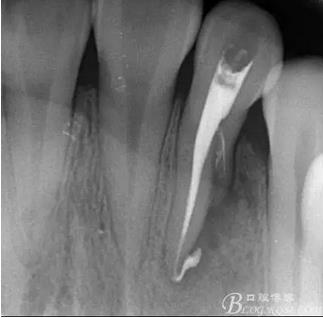

(1) 檢查:12唇側(cè)牙齦可見竇道,牙體顏色較鄰牙暗,無光澤,形態(tài)完整無缺損,唇側(cè)及近遠中向未提及牙周袋。腭側(cè)齦緣輕度紅腫,舌側(cè)窩可探及裂溝,可見浸墨狀痕跡,沿裂溝舌側(cè)探診牙周袋深大于11mm,除患牙外全口牙周狀況良好,為探及牙周袋,牙齦色粉紅。邊緣菲薄,質(zhì)地堅韌。12冷熱診無反應(yīng),叩診(+-),無明顯松動,無咬合創(chuàng)傷。12根尖x線片示,根管中三分之一中可見一斜向線樣透射影像根尖區(qū)及遠中根三分之一可見低密度透射暗影,錐形束CT示12根尖區(qū)唇腭向骨吸收已穿通,根面溝達根中三分之一卷曲分出另一牙根,再未見其他明顯的根管系統(tǒng)。

(6)復(fù)診:原暫封材料再位,牙周無明顯異常與不適,常規(guī)清潔根管,H銼清除根管內(nèi)維他,次氯酸鈉終末消毒,干燥根管,單尖測壓發(fā)充填根管,術(shù)后拍片到位。